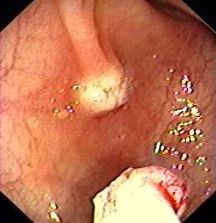

Magenspiegelung (Ösophago-Gastro-Duodenoskopie)

Zur Abklärung von Oberbauchbeschwerden, Schluckbeschwerden, Sodbrennen etc.

Testung auf Helicobacter pylorii

Endoskopische Entfernung von PEG Sonden (MagenSonden)

Endoskopische Tumornachsorge